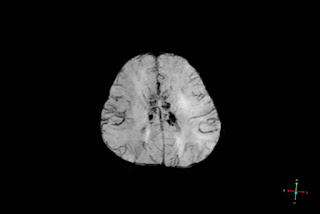

Case Report: 21 months pyrexic male with seizures & unconsciousness. MRI shows extensive, symmetrical, restricted diffusion lesions in cortical & subcortical white matter regions of supra & infra tentorial compartments in general particularly involving interhemispheric fissure, sylvian & central sulci locations, thalami, basal ganglia (most in putamen), corpus callosum (mainly splenium), brain stem(mainly pons), middle cerebellar peduncles, cerebellar hemispheres with reduced ADC values & blooming foci in SW (possible micro- haemorhage) with no perilesional edema or significant mass effect or midline shift, herniation- not specific to etiology, however could represent diffuse lesions variety of AESD ( acute encephalopathy with biphasic seizures & late reduced diffusion). DD- unusual HIE, substance toxicity related brain injury .

3. MRI could be normal for the first 48 hours . Later shows cortical edema & subcortical white matter bright signal on DW named “bright tree appearance” (days 3-9). Possible explanation is excitotoxicity, as evidenced by the increase in glutamine and glutamate complex detected by MR spectroscopy.